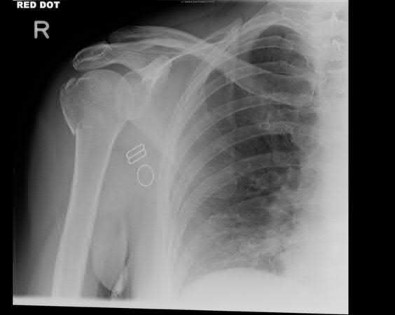

A 44-year-old male is struck by a vehicle while riding his bike. In the trauma bay, he complains of right shoulder pain . Upper extremity physical exam reveals no neurologic deficits, and an initial radiograph of the shoulder is shown in Figure A. A CT scan of the shoulder shows 1cm of posterior displacement of the tuberosity fragment. Which of the following is true regarding this injury?

The radiograph in Figure A demonstrates a posteriorly displaced greater tuberosity fracture. These injuries are often associated with anterior shoulder dislocations, and concomitant rotator cuff tears. The subscapularis attaches to the lesser tuberosity, and is not a deforming force. Open reduction and internal fixation (ORIF) is usually the treatment of choice, and it is well accepted that more than 5mm of displacement is an indication for surgery in patients that require overhead function of the arm.

Flatow et al evaluated 12 patients who were an average of five years status post ORIF of displaced greater tuberosity fractures. All fractures healed without postoperative displacement. Six patients had an excellent result and six had a good result.

Platzer et al retrospectively analyzed functional and radiographic results of 52 patients with operative treatment of displaced greater tuberosity fractures at an average time of 5.5 years from surgery compared to 9 patients with equivalent injuries treated non-operatively. Evaluation of the results of the surgical study group and the nonoperative control group, patients with reduction and fixat ion of greater tuberosity fractures had significantly better

results on shoulder function than did those with conservative treatment.